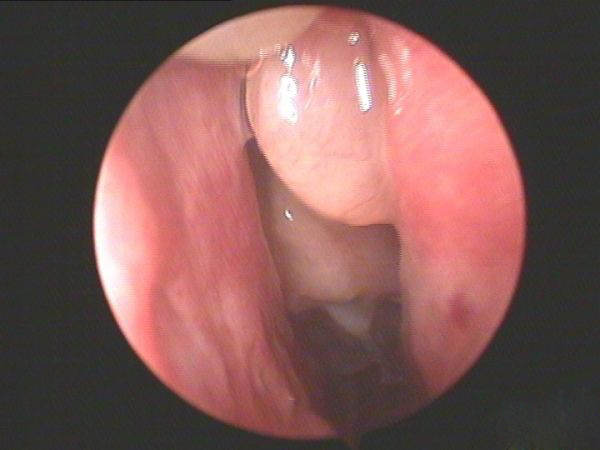

鼻息肉圖片

鼻息肉